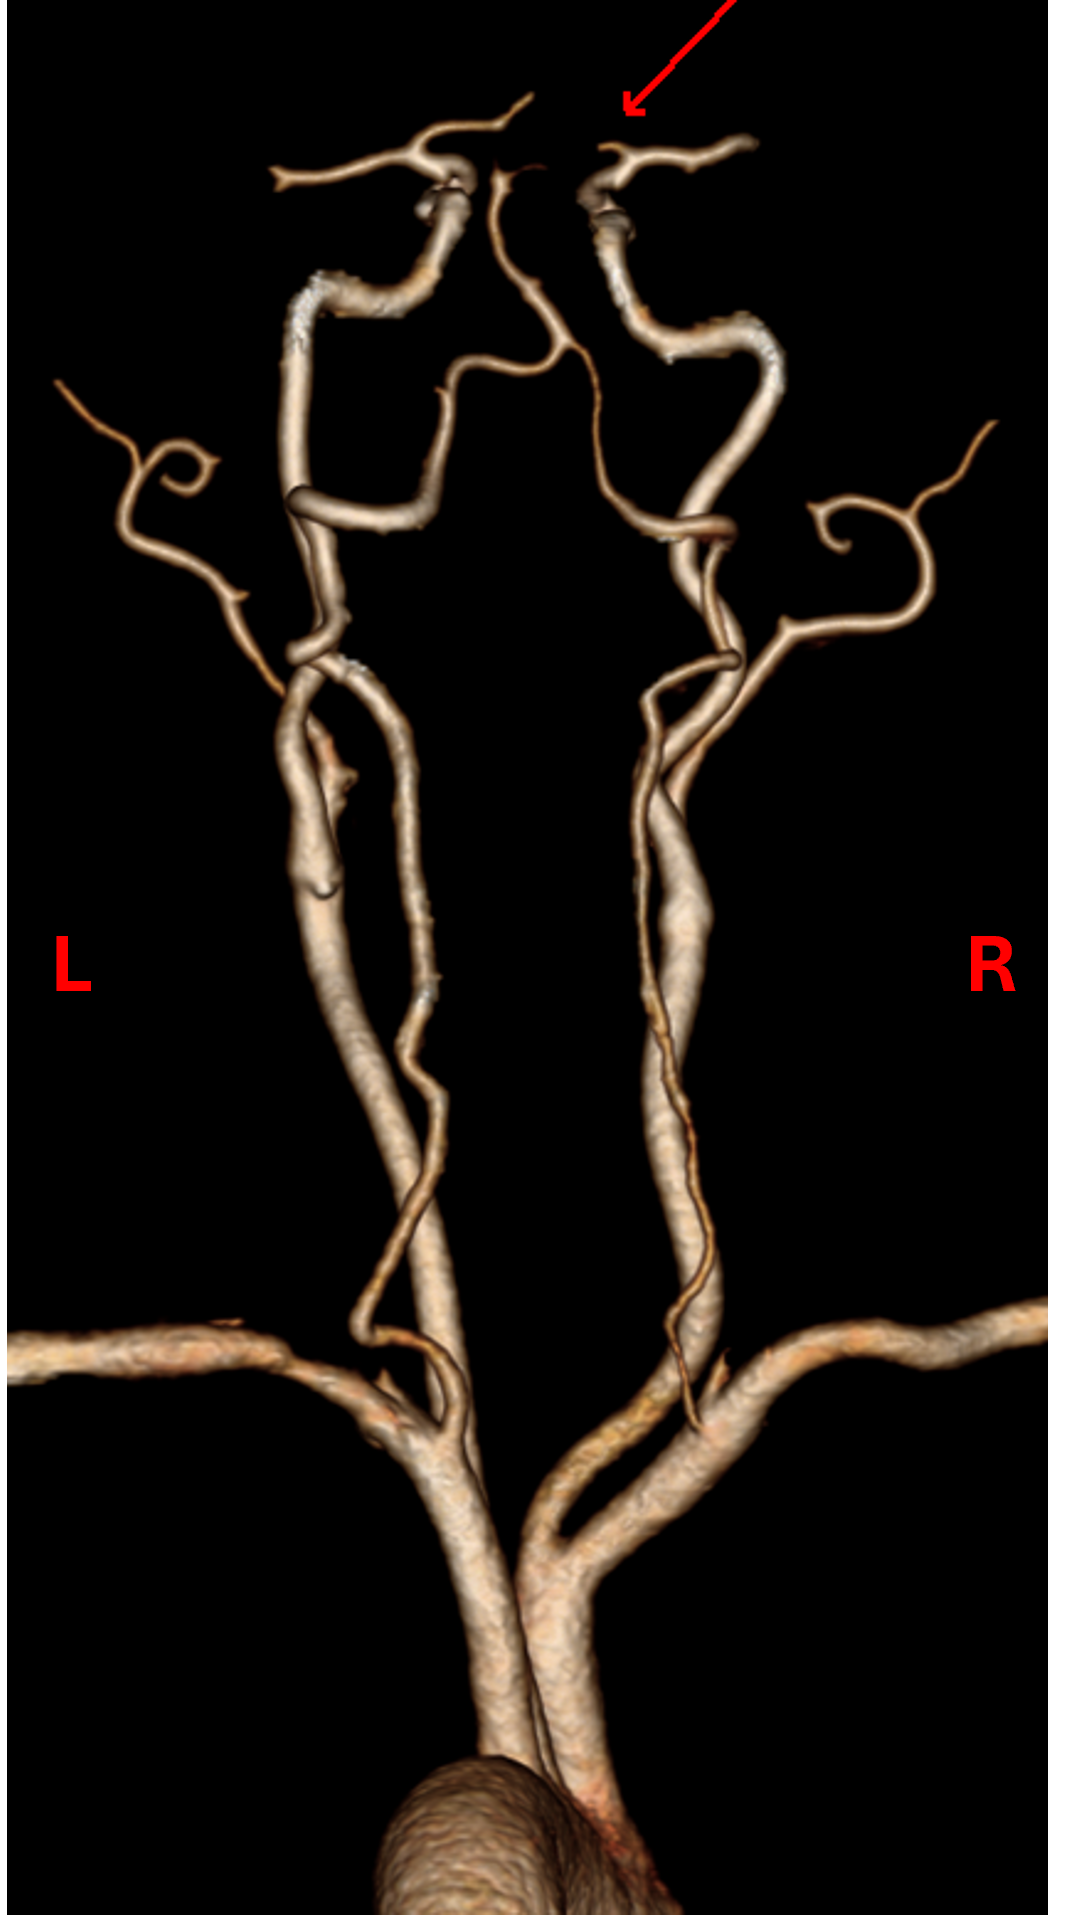

Case Presentation: A 67 year-old female presented to the ED with acute left upper extremity paresis and facial droop. She had 2 previous cardioembolic strokes, in 2007 from mitral nonbacterial thrombotic endocarditis for which she started warfarin and in 2010 after stopping warfarin for 8 months due to menorrhagia. Warfarin was switched to apixaban in 2021 due to patient preference. She also had atrial fibrillation (AF) with CHA2DS2-VASc 5 (diagnosed 2020), mild-moderate mitral regurgitation (on 2020 echocardiogram), hypertension, hyperlipidemia and a 37 pack-year smoking history.She was hypertensive (BP 172/89) with otherwise normal vital signs. Examination was significant for NIHSS 2 (left upper extremity drift and facial droop) and an irregularly irregular pulse. EKG confirmed AF. CT head and neck angiogram showed a proximal right M2 occlusion (Fig.1) with distal flow reconstitution and patent carotid arteries.Neurology, Vascular medicine and Cardiology teams were consulted. She was not a thrombolysis candidate due to apixaban intake and mild signs/symptoms. Apixaban peak and trough levels were both within the expected therapeutic range with anti-Xa levels of 130 and 77 respectively. Thrombophilia testing was negative for protein C, prothrombin gene mutation, factor V Leiden and antiphospholipid antibodies. Work-up for malignancy with CT imaging and cancer screening was unremarkable.Transesophageal echocardiogram was obtained to assess for a cardioembolic cause of stroke and revealed a hockey-stick appearance of the anterior mitral leaflet which is classic for rheumatic valve disease (Fig.2), moderate mitral stenosis and moderate mitral regurgitation. Ejection fraction was preserved at 50% and there was no intracardiac mass or patent foramen ovale.Apixaban had been inadequate anticoagulation as she now had both moderate rheumatic mitral stenosis and atrial fibrillation. She was bridged to warfarin with target INR 2-3 and discharged to valve clinic for follow-up.